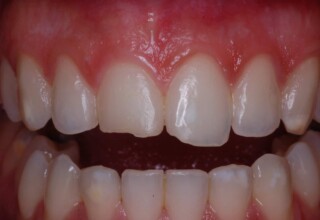

Δυσχρωμικοί άνω πλάγιοι τομείς

Αρχική εμφάνιση

Τελική εμφάνιση